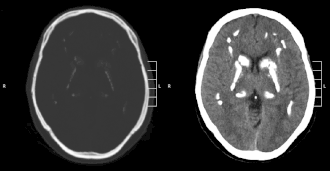

Description de cette image, également commentée ci-après

Décrit pour la première fois en 1951[1], le syndrome de Fahr est une maladie se traduisant par des calcifications massives des noyaux gris centraux en l'absence d'anomalie du métabolisme du calcium. Il existe parallèlement des signes neurodégénératifs.

La constatation de calcifications des noyaux gris centraux est fréquent dans de nombreuses maladies. Près de 1 pour cent des scanners du cerveau montrent la présence de calcifications des noyaux gris centraux surtout après 60 ans. Cette constatation ne s'accompagne pas d'une augmentation de pathologie neurologique chez ces individus.